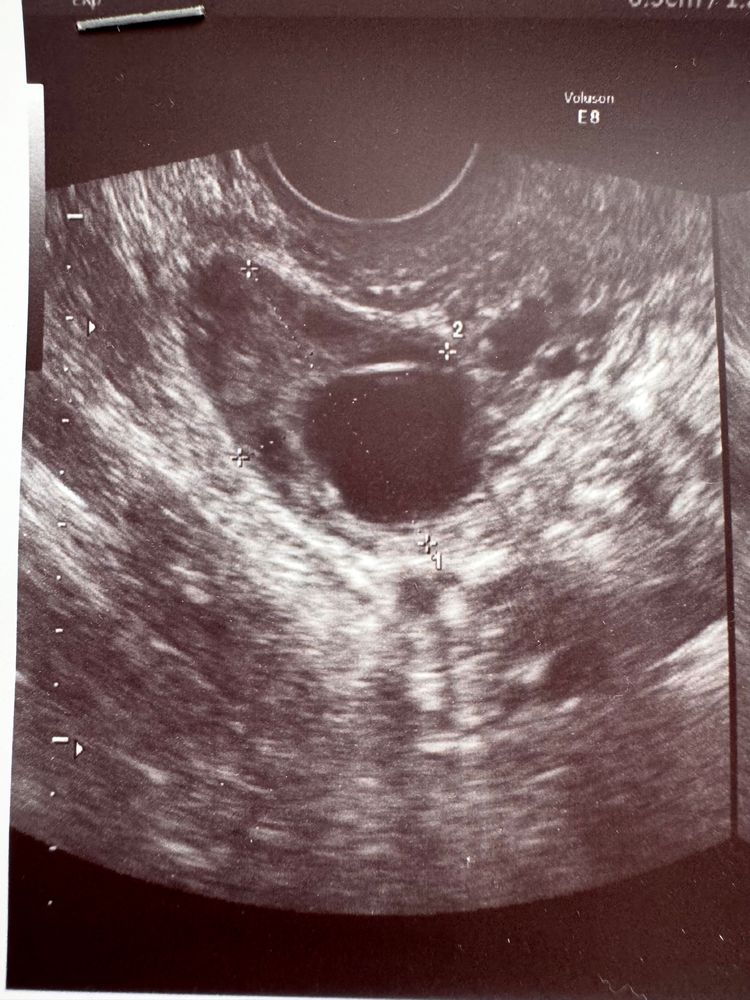

Это фолликул или желтое тело?

В прошлом цикле один узист назвал кистой желтого тела дом.фолликул, через 2 дня другой узист назвал желтое тело дом.фолликулом. Если тест на О был ярким в день узи, скорее всего это ДФ. По описанию есть жидкость в малом тазу? Если дф лопнул, то должна быть

Марина, тогда высока вероятность, что это ДФ

мне пару раз встречались такие горе узисты, которые сдувшийся несовулировавший фоллик принимали за жт 🤪 я бы верила тестам) посмотрите динамику а второй яичник спокойный? может двойная?

Похоже на ЖТ, у меня тоже полосатились тесты 2-3 дня после овуляции